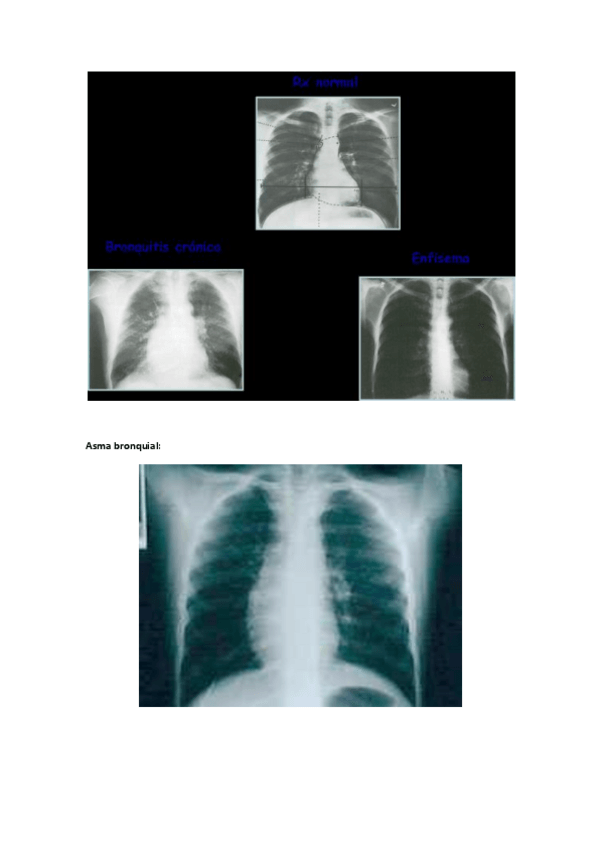

Afecciones Médicas I

Radiografias Ap.Respiratorio

Radiografias-Enfermedades-Ap.pdf